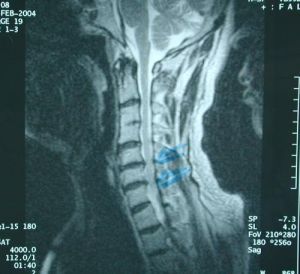

骨X線攝片在骨量減少>=30%時才顯示,有骨密度減低、骨小梁減少、骨小梁的間隙增寬、橫行骨小梁消失、骨結構模糊、椎體雙凹變形(因椎間盤膨脹所致)。椎體前緣塌陷呈楔形變,常分為Ⅲ級,Ⅰ級即輕度變形,指椎體前緣較後緣的高度矮20%~25%;Ⅱ級即中度變形,指椎體前緣較後緣的高度矮26%~39%;Ⅲ級為嚴重變形,椎體前緣變矮塌陷>=40%,亦稱壓縮性骨折,常見於第11、12胸椎和第1、2腰椎。股骨和肱骨上端及橈骨遠端也易見骨密度減低、皮質變薄、髓腔增寬和骨小梁減少等改變。

此病和內分泌因素、遺傳因素、營養因素、廢用因素等有關。骨質疏鬆較輕時常無症狀,往往偶由骨X線片而被發現椎體壓縮性骨折。峨遏手工藝搭椎體壓縮性骨折空位生後,立即出現該部位的急劇銳痛,常無明顯外傷史,可發生在咳嗽或打噴涕後,不給特殊治療3—4周后可逐漸緩解。另一種背部慢性深部廣泛性鈍痛,伴全身乏力等。疼痛常因脊柱彎曲、椎體壓縮性骨折和椎體後突引起。椎體壓縮性骨折引起身高縮短和導致脊柱後突,脊柱後突又可引起胸廓畸形,影響肺功能。骨折的部位以錐體、髖骨和撓骨遠端為多見。